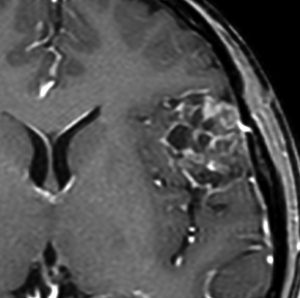

angiomatous meningioma WHO grade 1 血管腫様髄膜腫

術前検査ではまるで膠芽腫のような画像です。でも,開けてみれば髄膜腫ということはすぐにわかる肉眼所見です。硬膜の至る所から腫瘍血管が流入して出血性腫瘍です。

多数の小血管から構成される組織像です。右のvimentin染色は陽性です。

核小体明瞭な大小不同な類円形核からなる細胞境界が不明瞭な腫瘍細胞がみられ,ヘモジデリン貪食マクロファージも認められます。MIB-1染色率は2-3%でグレード1です。